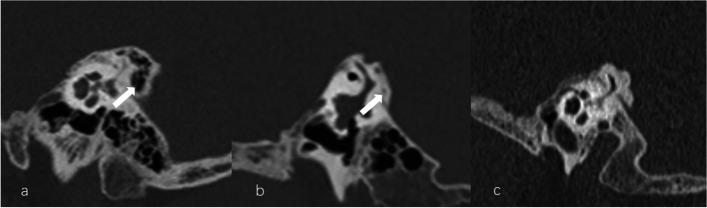

The vestibular aqueduct (VA) serves an essential role in homeostasis of the inner ear and pathogenesis of Ménière's disease (MD). The bony VA can be clearly depicted by high-resolution computed tomography (HRCT), whereas the optimal sequences and parameters for magnetic resonance imaging (MRI) are not yet established. We investigated VA characteristics and potential factors influencing MRI-VA visibility in unilateral MD patients.

METHODS

One hundred patients with unilateral MD underwent MRI with three-dimensional sampling perfection with application optimized contrasts using different flip angle evolutions (3D-SPACE) sequence and HRCT evaluation. The imaging variables included MRI-VA and CT-VA visibility, CT-VA morphology and CT-peri-VA pneumatization.

RESULTS

The most frequent type of MRI-VA and CT-VA visualization was invisible VA and continuous VA, respectively. The MRI-VA visibility was significantly lower than CT-VA visibility. MRI-VA visibility had a weak positive correlation with ipsilateral CT-VA visualization. For the affected side, the MRI-VA visualization was negatively correlated with the incidence of obliterated-shaped CT-VA and positively with that of tubular-shaped CT-VA. MRI-VA visualization was not affected by CT-peri-VA pneumatization.

CONCLUSION

In patients with MD, the VA visualization on 3D-SPACE MRI is poorer than that observed on CT and may be affected by its osseous configuration. These findings may provide a basis for further characterization of VA demonstrated by MRI and its clinical significance.